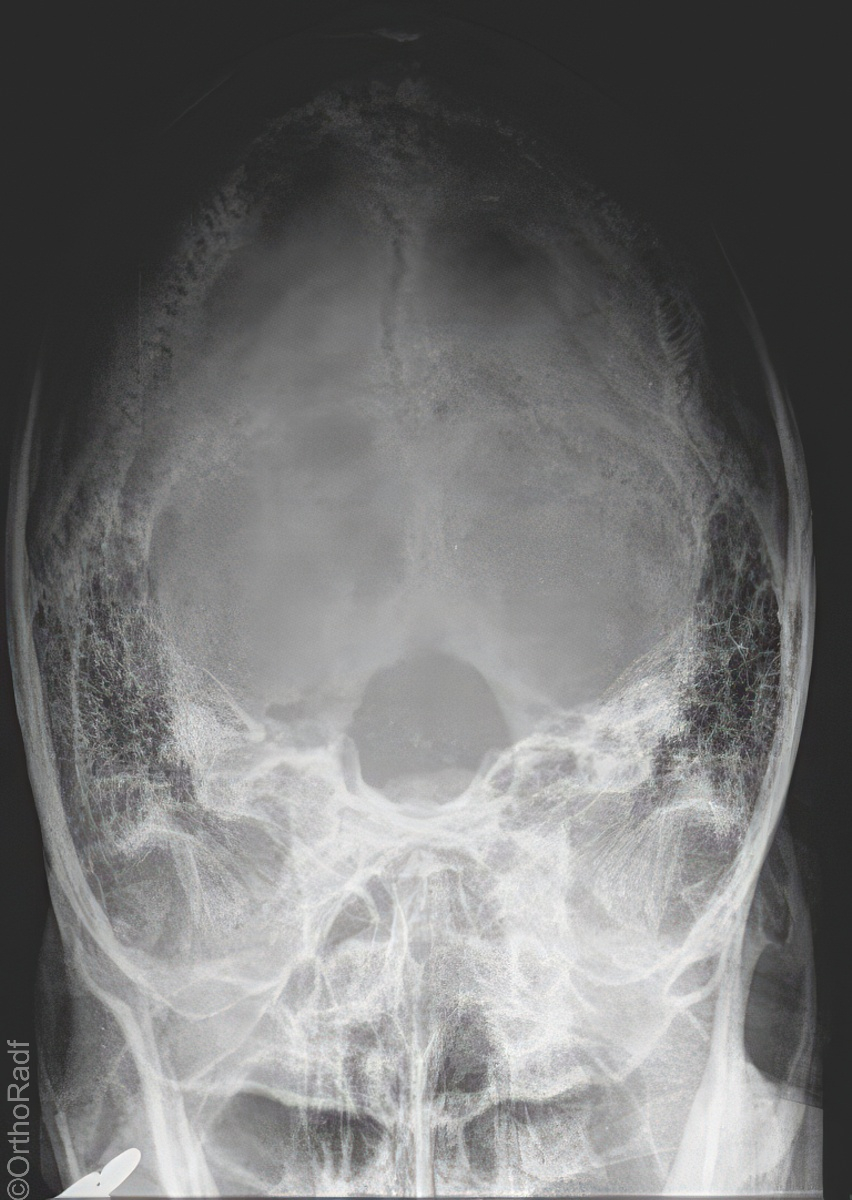

Schädel occipital

Technik

• FDA: 1,15 m

• Ausgangsformat: 24/30 hoch

• mit Raster

• Röhrenkippung: 45° cranio-caudal

Lagerung

Patient liegt auf dem Rücken, das Kinn (Doppelkinn) so weit wie möglich zu Brust gezogen.

Zentralstrahl

zielt mit 45° cranio-caudal vom Scheitel (Bregma) zum ertasteten Hinterhaupt (Occiput). Objektmitte

Qualitätskriterien

Freie Darstellung des gesamten Hinterhauptes mit Foramen magnum, hier sollt auch der hintere Atlasbogen projiziert werden. Symmetrische Darstellung der Pyramiden.